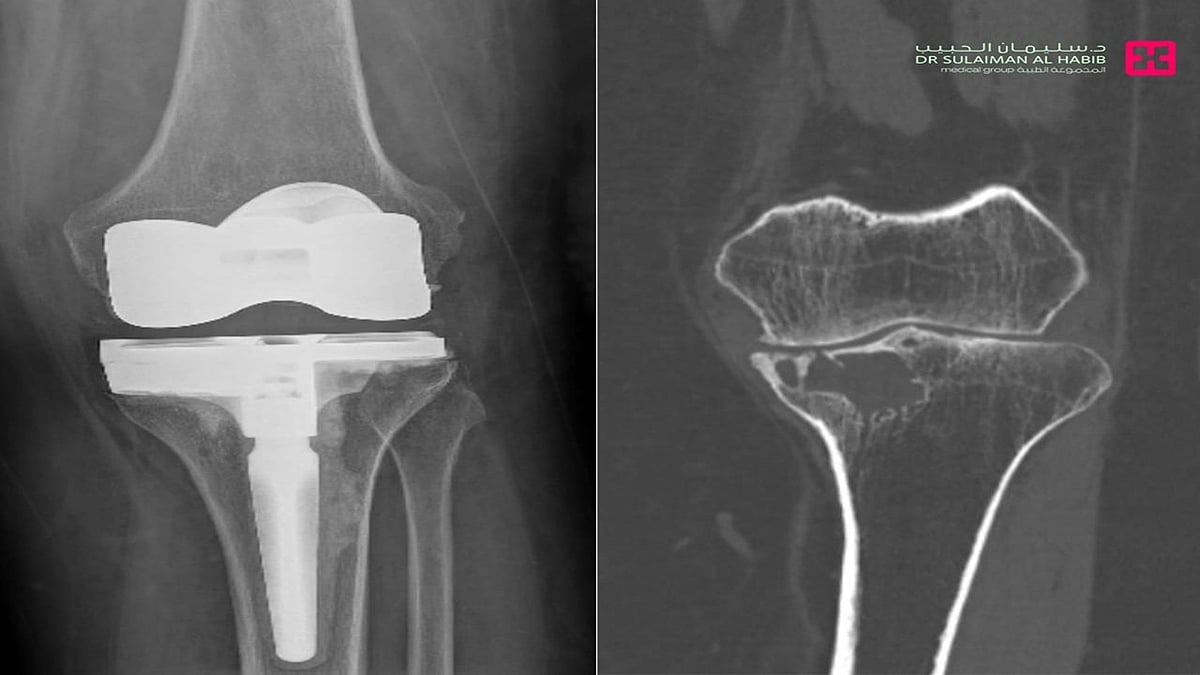

مستشفى الدكتور سليمان الحبيب بالفيحاء في جدة يجري جراحة معقدة لاستئصال ورم واستبدال مفصل الركبة لأربعينية

أجرى مستشفى الدكتور سليمان الحبيب بالفيحاء في جدة، عملية معقدة لاستئصال ورم دموي واستبدال مفصل الركبة، لمراجعة تبلغ من العمر 48 عاماً ، تشتكي من ألم شديد في الركبة يمنعها من المشي وممارسة نشاطها اليومي. ذكر ذلك الدكتور أنس نوح استشاري طب وجراحة العظام والمفاصل، رئيس الفريق الطبي المعالج الحاصل على الزمالة الكندية.